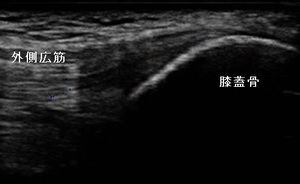

右膝外側 超音波長軸像 左同部 正常(健)側

その後、当接骨院を受診。右膝の上外側に圧痛、叩打痛、屈伸時痛が著明でした。超音波観察を行ったところ、

整形外科で「お皿の骨が分かれている」と言われたことが、有痛性分裂膝蓋骨であったことが分かりました。

(左上画像の矢印)

痛みのある状態を言います。男子は、超音波観察から膝蓋骨の上外側に診られるⅢ型と認められました。